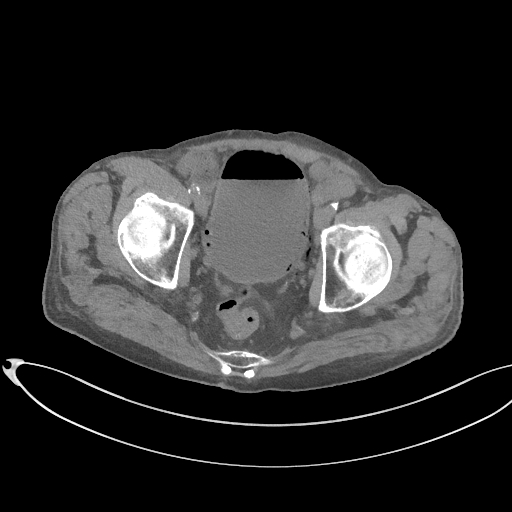

Figurile 3 şi 4: sagital examinare CT abdomen şi pelvis fără substanță de contrast

Discuţie caz nr 131: pacient de 85 de ani cunoscut diabetic este adus la camera de gardă pentru dureri abdominale difuze, efectueaza CT fără substanță de contrast deoarece eGFR este 21 mL/min/1.73 m². Se evidențiază pericardita în cantitate medie, mai multe chiste renale – unul spontan hiperdens, multiple plăci aterotrombotice calcificate la nivelul aortei și ramurilor precum și multiple bule aerice în peretele vezicii urinare și conținut hidro-aeric al vezicii urinare. Ultimele două elemente sugerează diagnosticul de cistita emfizematoasă.